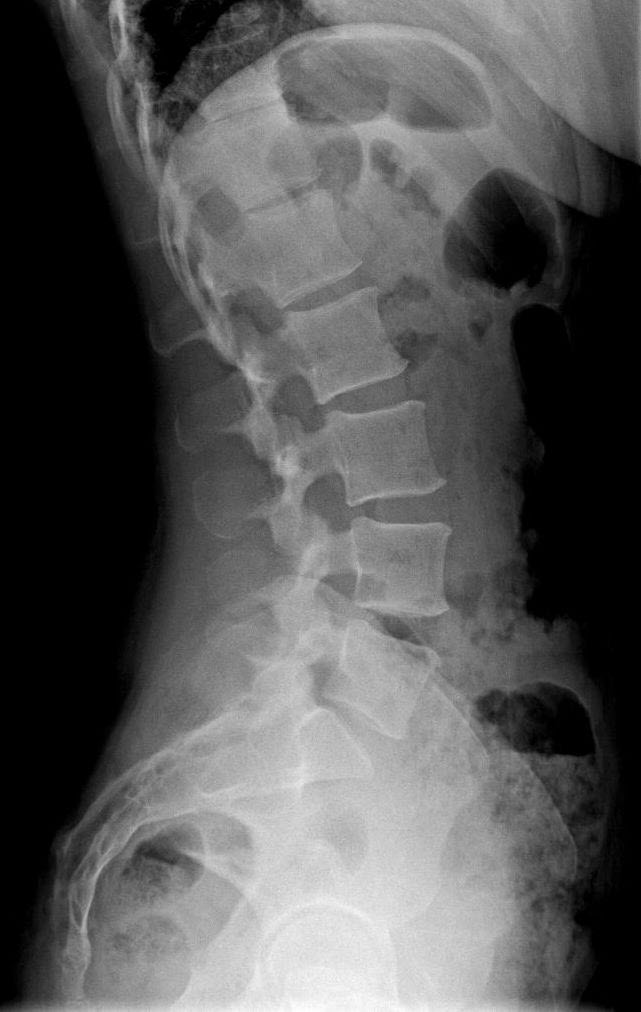

Degenerative Disc Disease Progression, Symptoms, and Chiropractic

Degenerative Disc In Thoracic Spine How To Prevent Disc Degeneration From Getting Worse The discs that support your spine are often referred to. Here are a few ways to slow down ddd and preserve. Degenerative disc disease is one of the most common sources of back pain as you age, but it doesn’t have to be inevitable. Generally, once the cascade of microscopic changes that result in ddd have started, there is nothing. How To Prevent Disc Degeneration From Getting Worse.

Thoracic Degenerative Disc Disease NJ & NYC How To Prevent Disc Degeneration From Getting Worse From poor posture to eating certain foods, learn the top seven things to avoid with degenerative disc disease for prevention and to. Spinal traction to ease muscle tightness and nerve compression. Generally, once the cascade of microscopic changes that result in ddd have started, there is nothing that. The discs that support your spine are often referred to. Excess body. How To Prevent Disc Degeneration From Getting Worse.